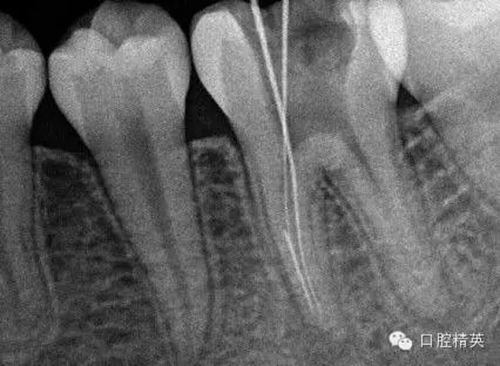

5, 插針確定斷針根管,為近舌根管,插針有阻力,EDTA封存一周復(fù)診。。。